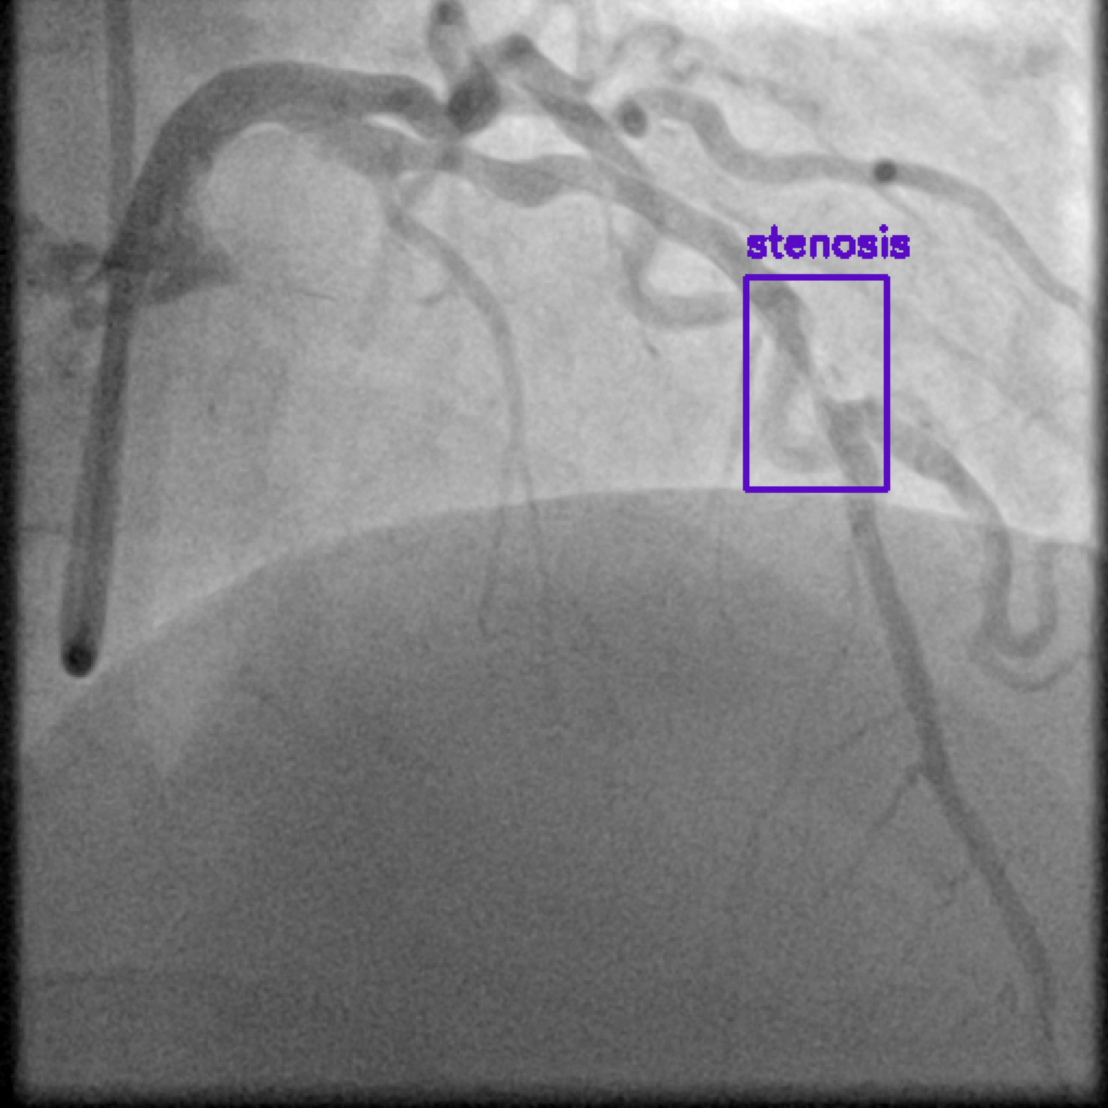

Figure 1 shows sample images from the ARCADE dataset with annotations for stenosis detection. The annotations highlight regions of arterial narrowing, providing ground truth data for training and evaluating object detection models.

To further assess the detection performance, qualitative results for three test images are presented in Figure 2. The first column shows the original images with ground truth annotations. The second, third, and fourth columns depict detections from DINO-DETR, Grounding DINO, and YOLO, respectively.

(a) Original (b) DINO-DETR (c) Grounding DINO (d) YOLO

The qualitative comparison in Figure 2 reinforces the trends observed in the quantitative evaluation. DINO-DETR produced fewer detections, occasionally missing relevant stenotic regions, consistent with its conservative detection strategy aimed at minimizing false positives [6]. Grounding DINO, although capable of identifying more regions, sometimes resulted in cluttered predictions due to over-detections [7]. YOLO provided a reasonable trade-off by effectively capturing anatomical structures while maintaining relatively high confidence scores and clear visualizations [5].